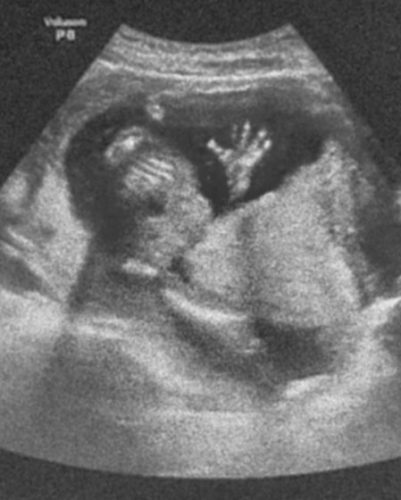

Joanne肚子里的小baby手掌像在跟大家Say Hi,太可爱了!